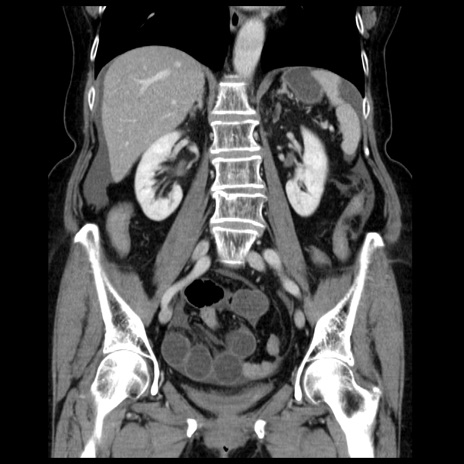

症例13(冠状断像)

【症例】70歳代女性

【主訴】腹痛、嘔吐

【現病歴】15時間程前(昨晩)より腹痛あり。今朝になっても症状の改善なく、嘔吐あり。腹痛も増悪あり、救急外来受診。

【既往歴】子宮癌全摘術後

【身体所見】意識清明、BP 121/72mmHg、P 74bpm、SpO2 100%(RA)、腹部:平坦・軟、腸雑音ほぼ聴取せず。下腹部・心窩部・臍左上に圧痛あり。反跳痛なし。

【データ】WBC 10600、CRP 0.15